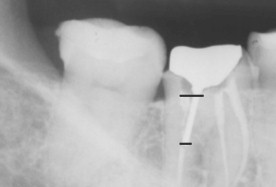

|

Control

radiográfico final. Nótese la radiodensidad de los postes de fibra

de vidrio similar a la de los tejidos dentarios, si los comparamos con

postes metálicos. |